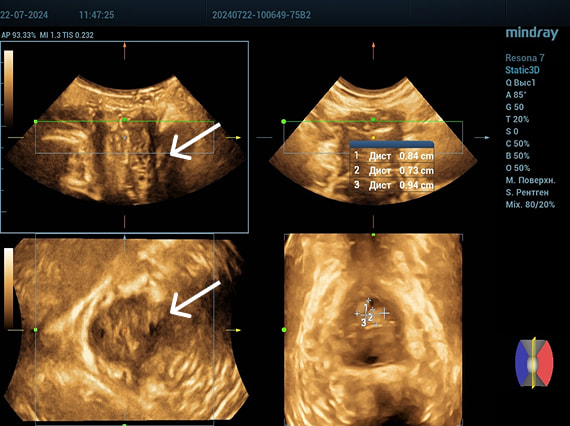

Осмотр: периуретрально визуализируется мягко-эластичное образование размерами 0,5×0,5 см.

Диагноз: хронический цистит (посткоитальный). Дистопия уретры. Опущение передней стенки влагалища I степени. Состояние после периуретрального введения геля на основе гиалуроновой кислоты.